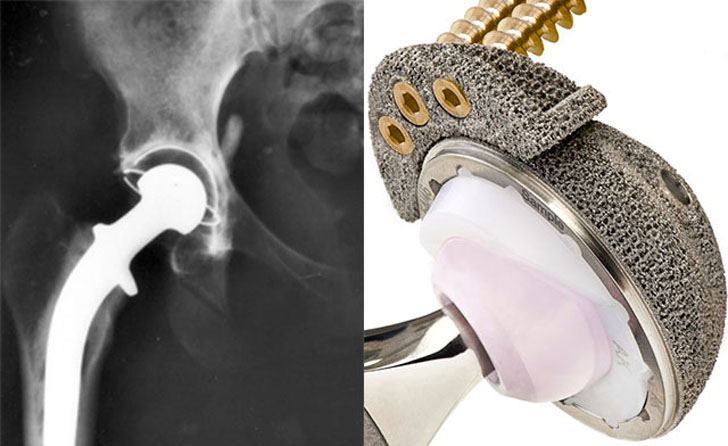

China Food & Drug Administration Approves 3D Printed Hip Implants For

3dprint.com

3dprint.com

3d hip implants printed china 3dprint fda approves printing drug administration manufacturing additive use food medical

China Approves 3D Printed Hips - 3D Printing Industry

3dprintingindustry.com

3dprintingindustry.com

3d hip printed china replacement approves functioning fully use

China Approves The Use Of 3D Printed Hip Replacement – Geeetech

www.geeetech.com

www.geeetech.com

3d printed hip replacement china printing joint approves use geeetech implant patients functioning fully